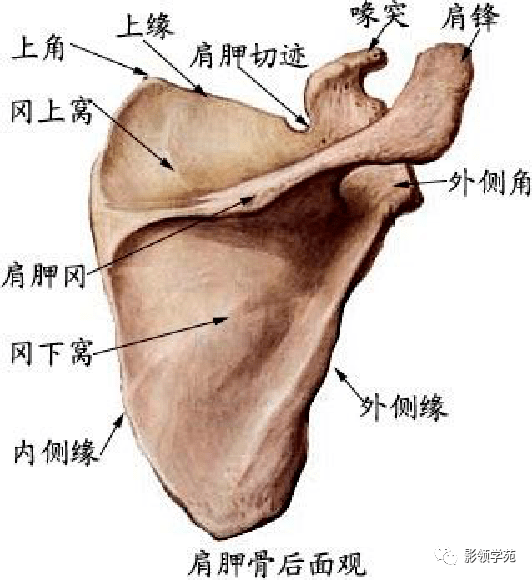

骨骼系统

骨骼系统